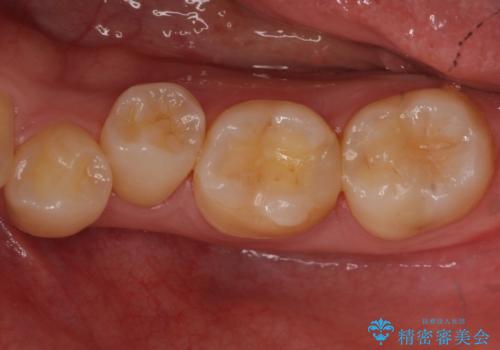

奥歯の詰め物の変色 セラミッククラウンでのやり替え

- 左下に詰めた樹脂の変色を主訴に来院されました。

同じ樹脂の材料で詰め直しをしたところでまた変色してしまうリスクが高いため、セラミックでの治療となりました。